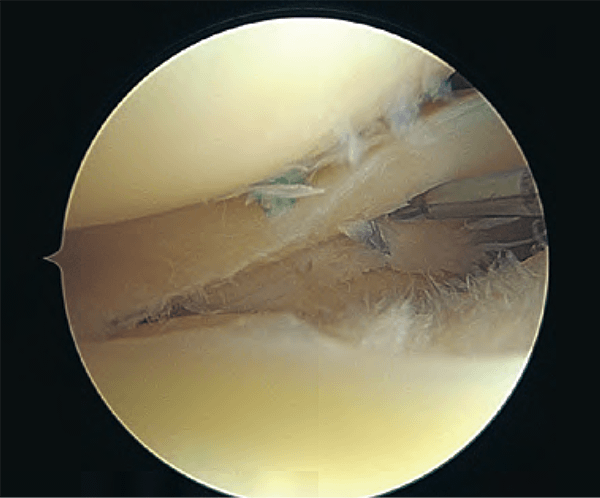

半月板のすべて−解剖から縫合手術,再生治療まで | 宗田 大, 関矢 一郎。半月板のすべて−解剖から縫合手術,再生治療まで | 宗田 大, 関矢 一郎。Ortho cutting edge:鏡視下半月板修復術(縫合術)の各種方法と。「半月板のすべて 解剖から手術、再生医療まで」宗田 大 / 関矢 一郎 / 古賀 英之メジカルビュー社定価: ¥ 13200裁断済みです。。建築基準法 関係法令集 2024年版。裁断にご理解頂ける方のみご購入よろしくお願いします。密教占星術大全 : 『宿曜経』現代語訳総解説

• Ortho cutting edge:鏡視下半月板修復術(縫合術)の各種方法と